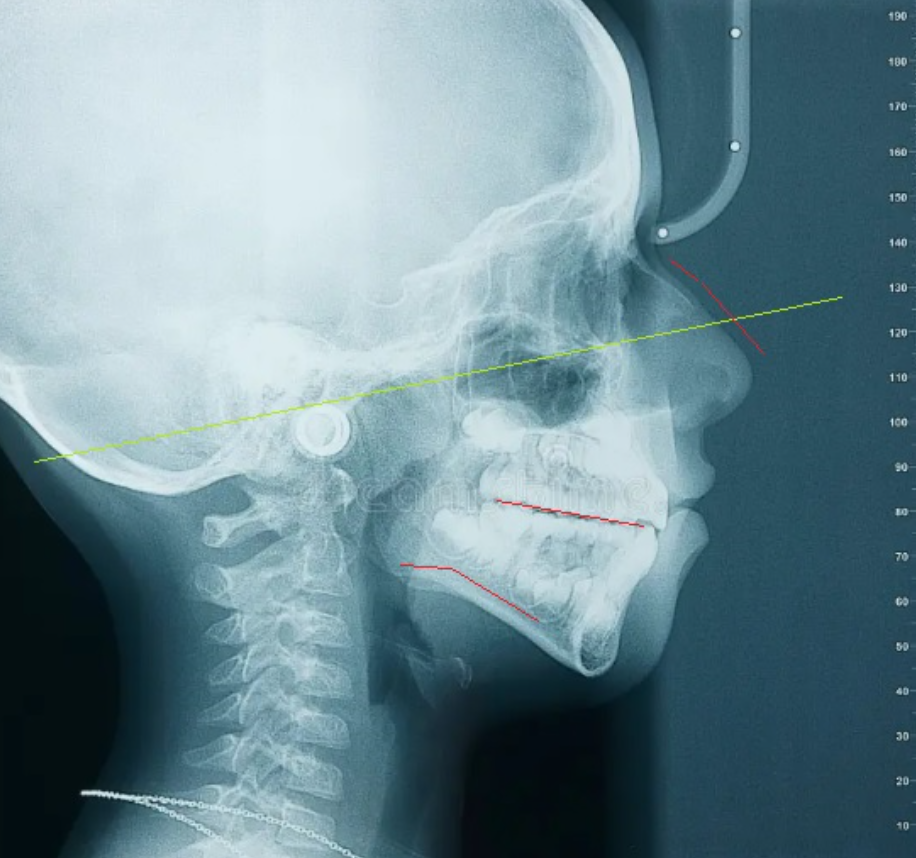

Image 4: Adenoid face with a slightly angled malocclusional plane caused by natural backwards and downwards rotation of the mandible/maxilla due to inactivity of the masticators. Impacts airways. Notice the head is tipped upwards (relative to image 2 especially) to artificially open the airways. Subject has poor but necessary posture.

Image 5: Normal face with a horizontal malocclusional plane. This is what you guys know as "forward growth," but is really just optimal development of the masticators preventing backwards and downwards rotation of the mandible. Does not impact airways. One of the best health indicators of all time.

Xray

REAL LIFE:

Optimal: